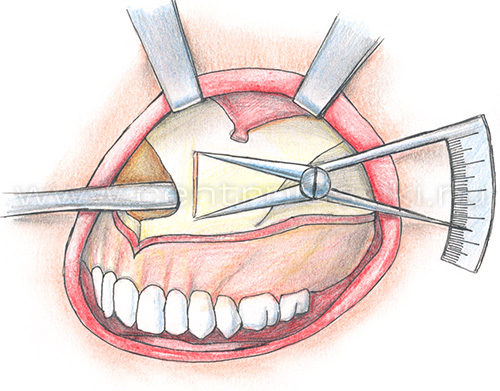

Остеотомия верхней челюстиПоказания Коррекция аномалий развития верхней челюсти (микрогнатия, ретрогнатия верхней челюсти). Остеотомию на верхней челюсти проводят как этап ортодонтического лечения. Операция Остеотомия верхней челюсти выполняется внутриротовым доступом под эндотрахеальным наркозом, выполняется разрез слизистой оболочки полости рта и надкостницы, разрез производят несколько выше переходной складки верхней челюсти от 7 до 7 зубов. Края раны раздвигаются, тем самым осуществляется доступ к передней стенке верхней челюсти.  На передних и боковых стенках верхней челюсти слева и справа производятся разметки линий распилов.  Специальными пилками проводится остеотомия по разметкам.  Затем отделяется распиленный фрагмент и перемещается в заранее выбранное положение.   Фиксация перемещенного фрагмента в новом положении осуществляется титановыми мини-пластинками.  Длительность Операция занимает от 1,5 до 3 часов и проводится под наркозом. В течение 1 месяца после лечения сохраняется отечность мягких тканей лица, может отмечаться нарушение чувствительности верхней губы и щек, чувствительность восстанавливается самопроизвольно через некоторое время. В ряде случаев после операции для обеспечения хорошего срастания костей проводят межчелюстное шинирование , верхняя и нижняя челюсти фиксируются друг к другу специальными приспособлениями, так что полное открытие рта невозможно. В этот период (2-3 недели) возможно питание только протертой и жидкой пищей. После операции остеотомии верхней челюстиВ послеоперационном периоде возможно ношение ортодонтической брекет системы для правильного смыкания зубных рядов верхней и нижней челюстей. Реабилитационный период В течение 1-3 суток после операции рекомендовано нахождение в стационаре под наблюдением медицинского персонала (длительность нахождения в стационаре может быть продлена до 10 суток в зависимости от течения послеоперационного периода). Длительность реабилитационного периода зависит от восстановительных способностей организма. Эффективность Окончательный результат операции можно наблюдать через 3-6 месяцев. В послеоперационном периоде могут сохраняться отеки в течение 2-4 недель, в зависимости от индивидуальных особенностей восстановление протекает с разной скоростью. |